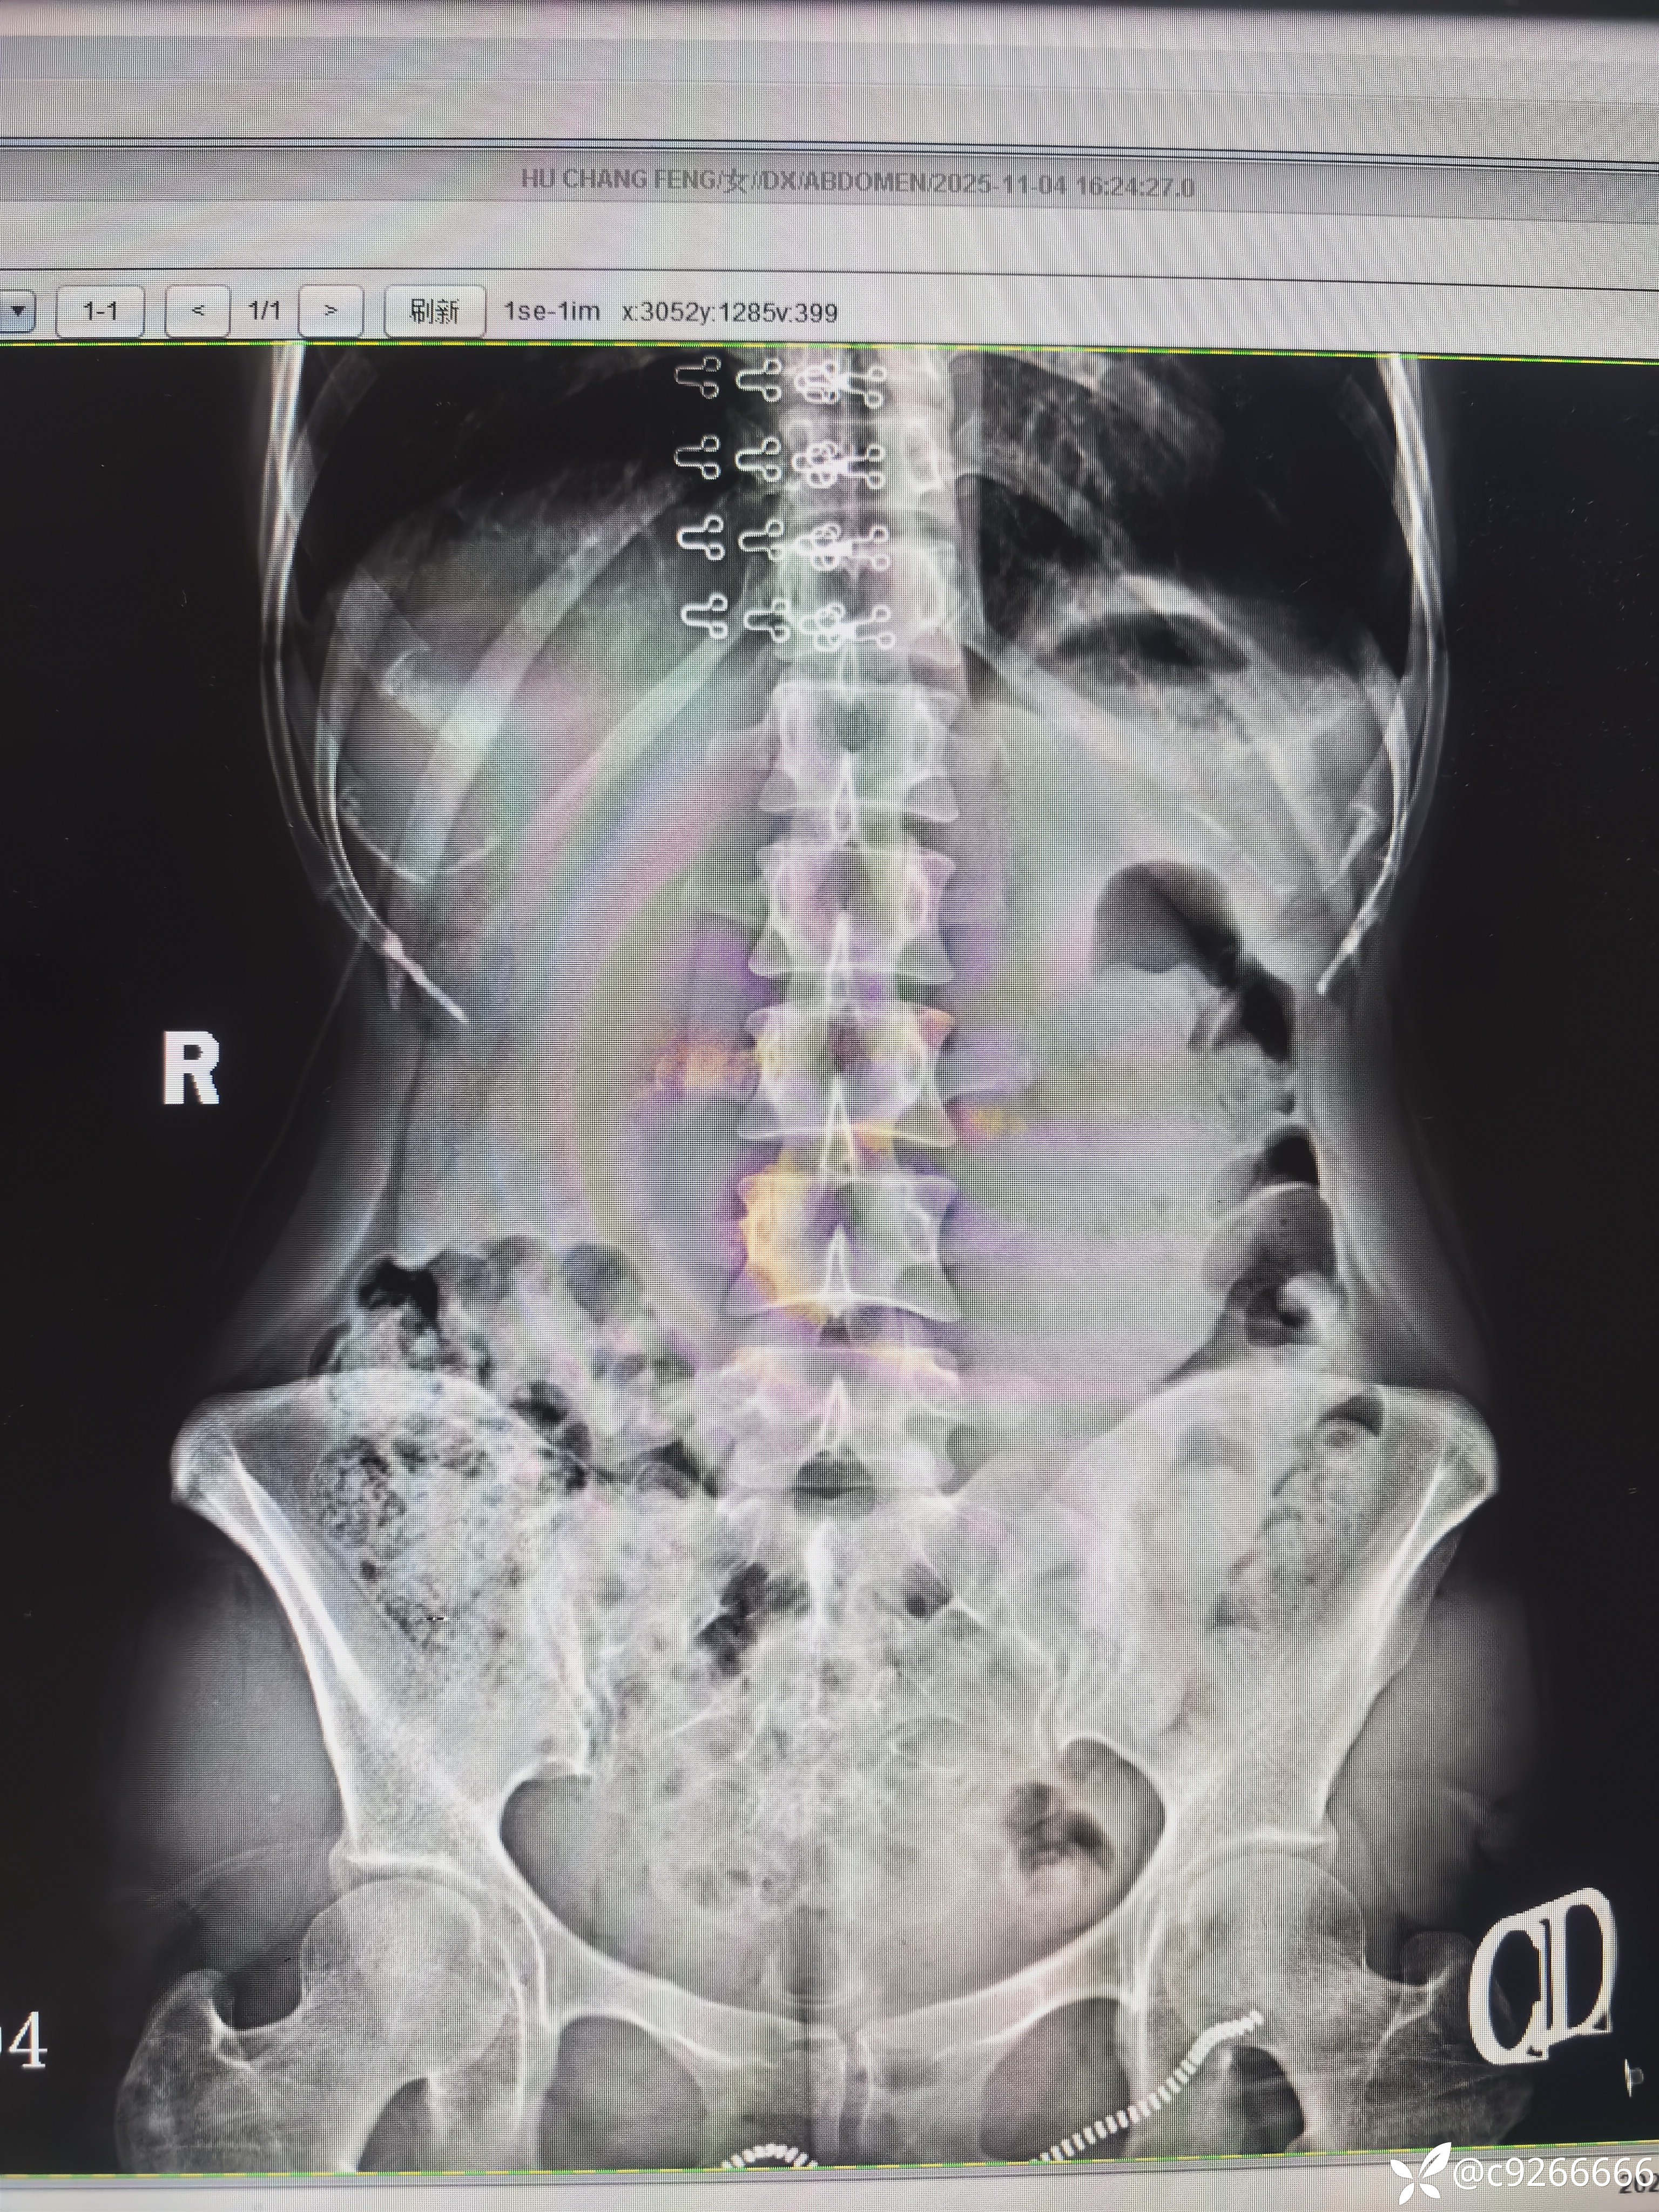

病例站立后下腹部彭隆一月

患者自感内脏在站立的时候全部掉落在下腹部。平躺后正常。